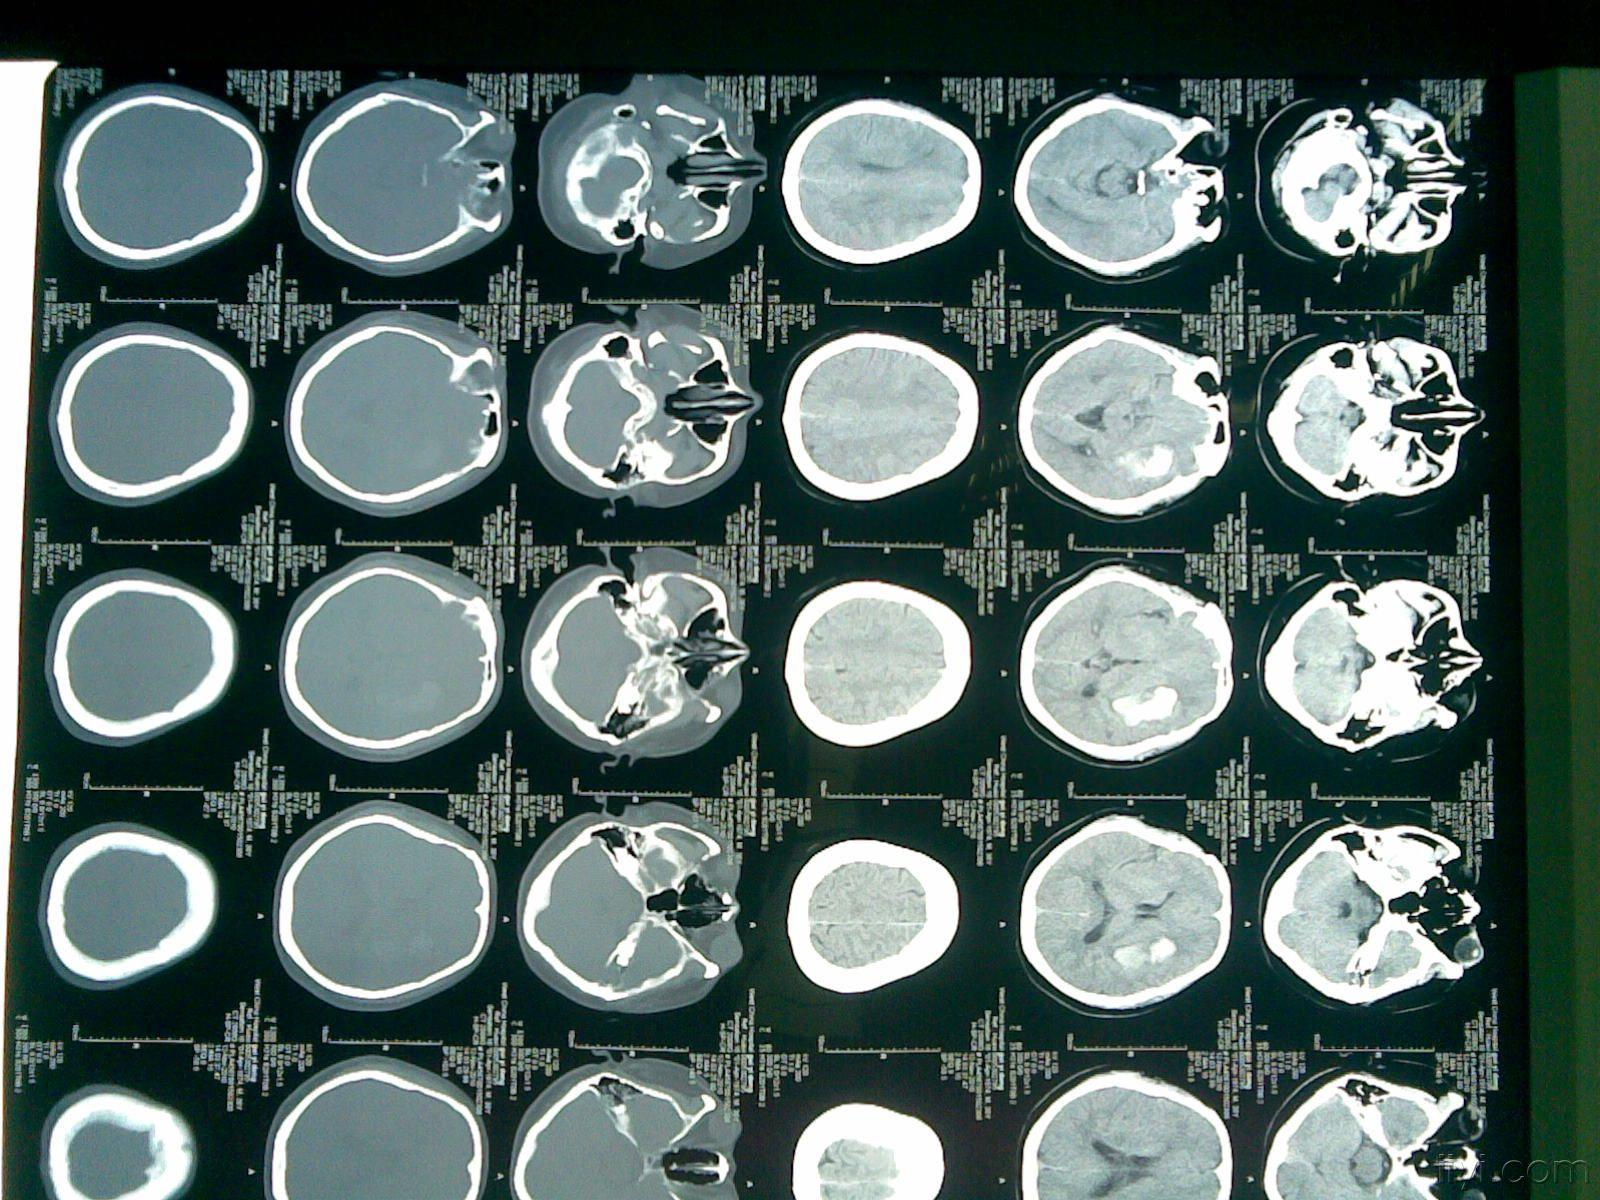

跪求 我妈妈76岁无脑病血压平常不太高 5月22日晚突发脑出血(脑室1-4